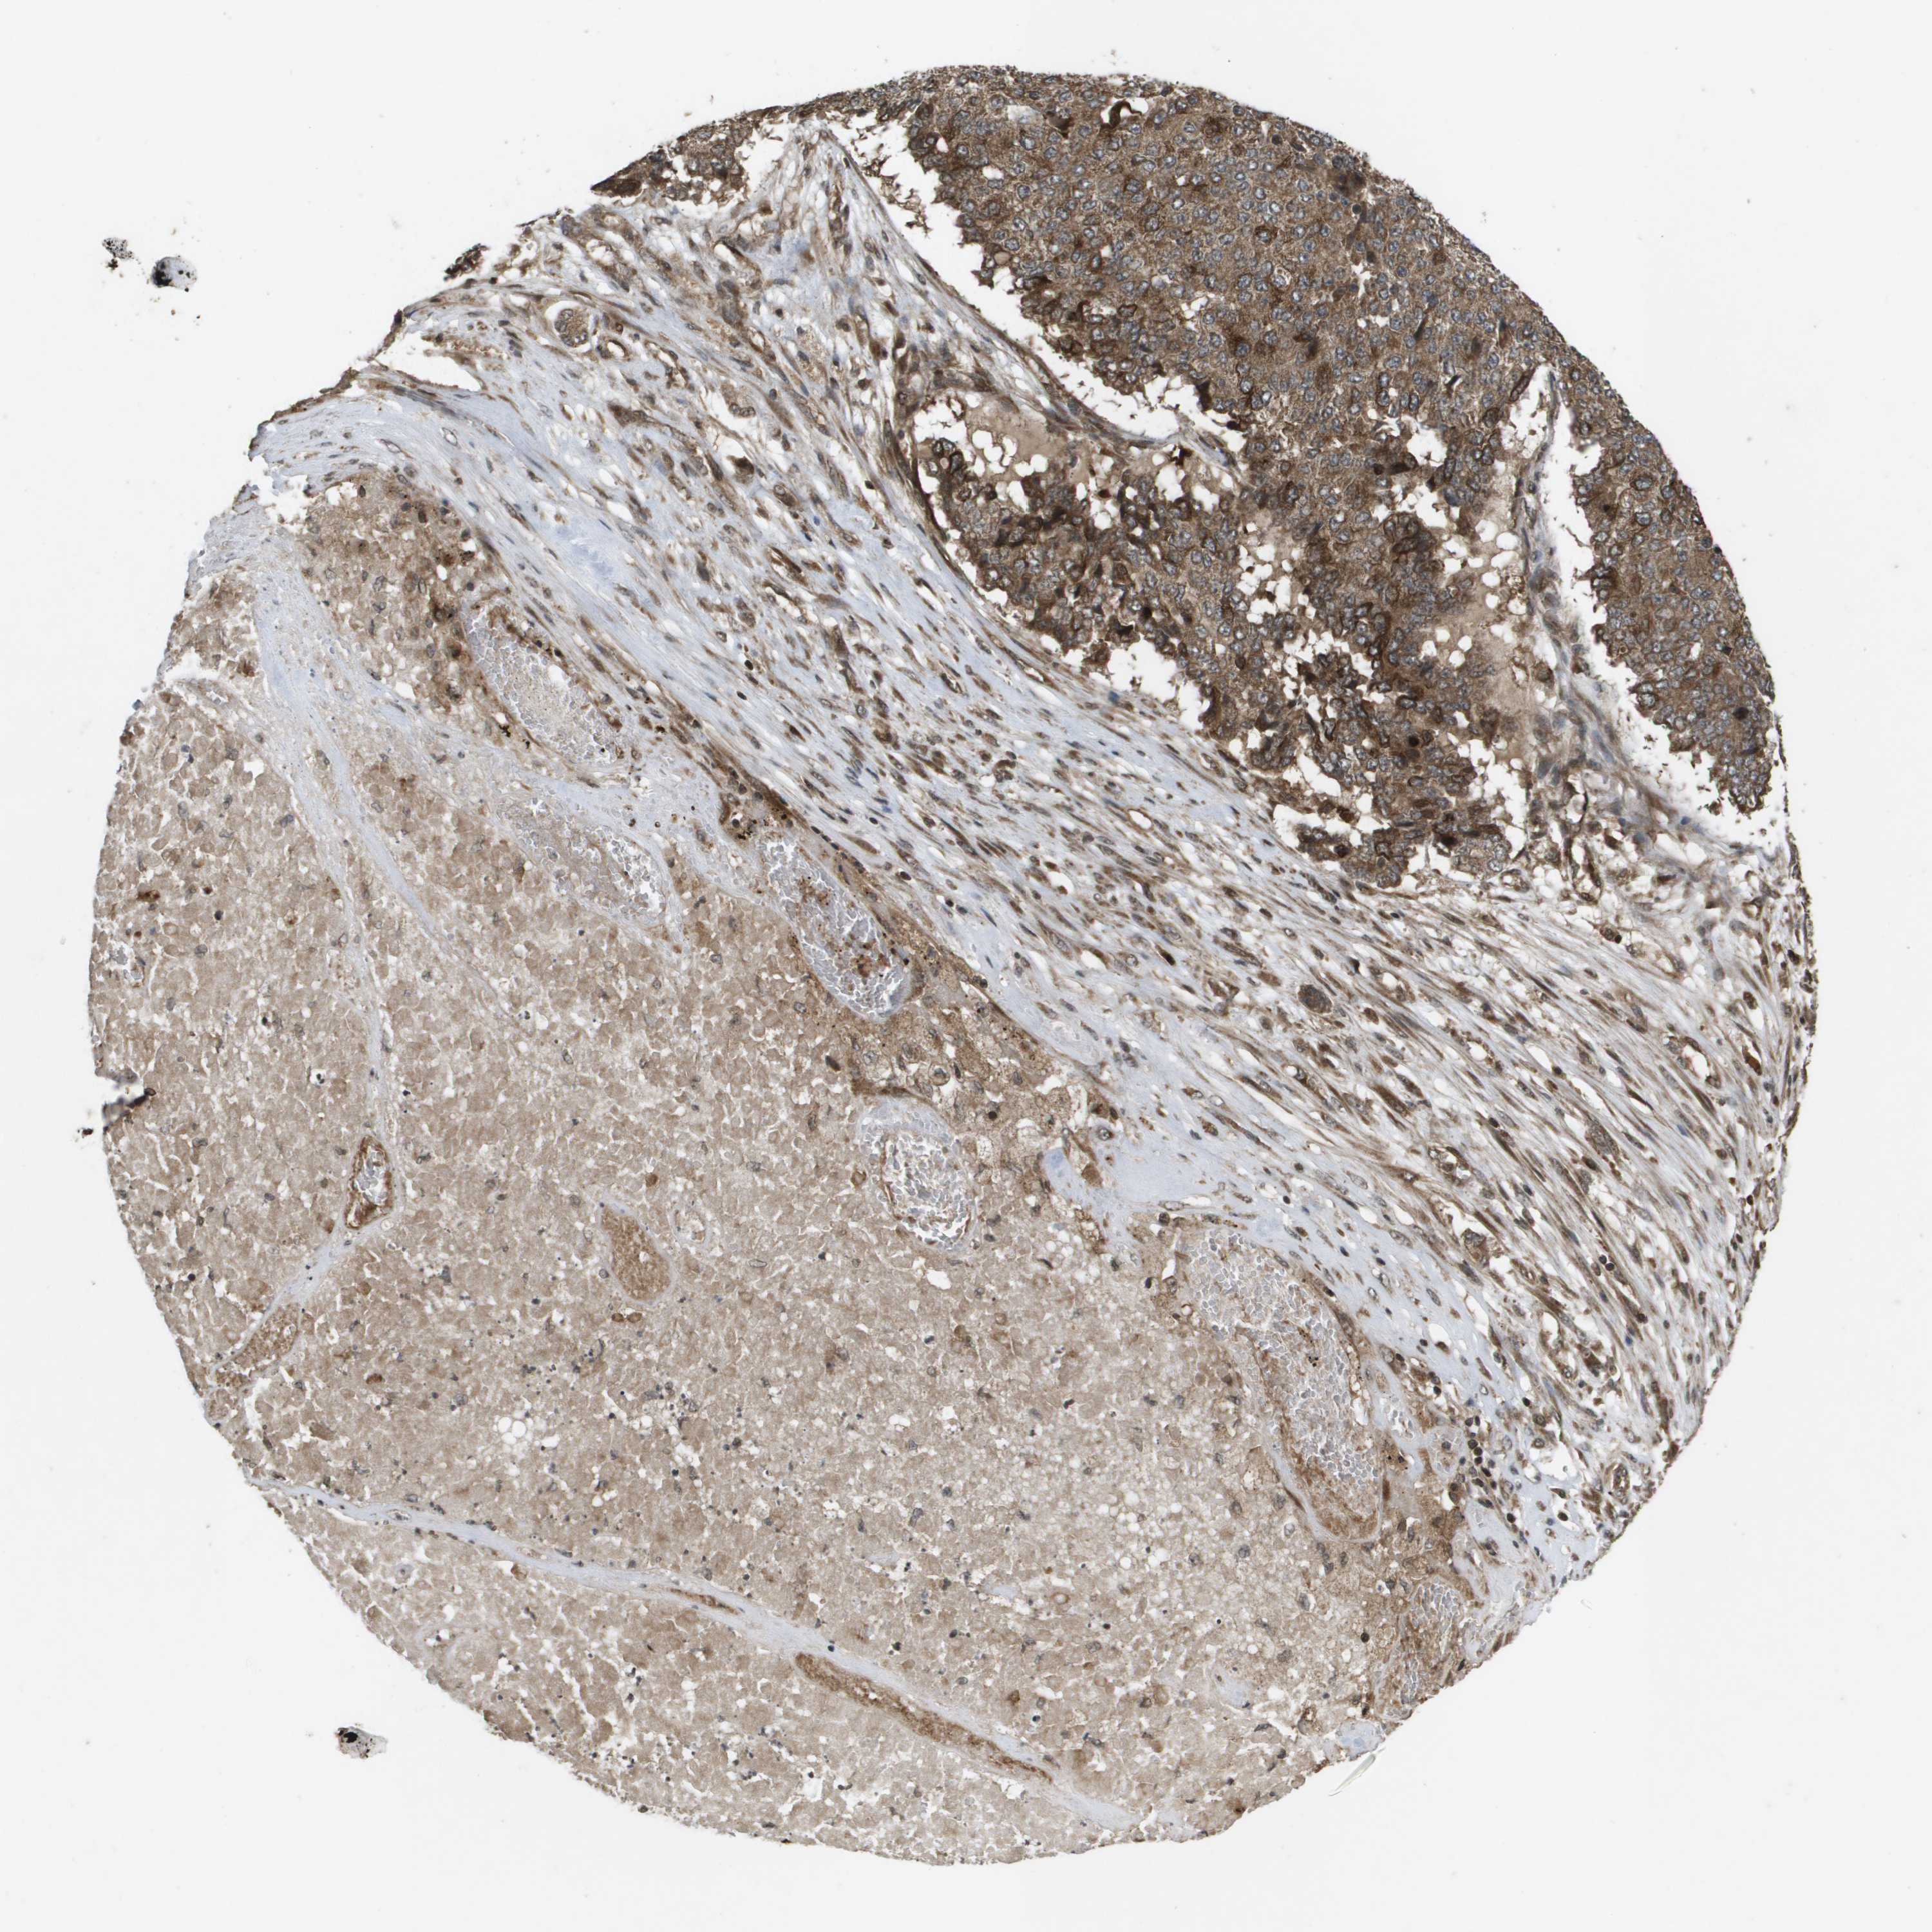

PANCREATIC CANCER - Protein expressioni

A mouse-over function shows sample information and annotation data. Click on an image to view it in a full screen mode. Samples can be filtered based on level of antibody staining by selecting one or several of the following categories: high, medium, low and not detected. The assay and annotation is described here.

Note that samples used for immunohistochemistry by the Human Protein Atlas do not correspond to samples in the TCGA dataset.

Antibody stainingi

Antibody staining in the annotated cell types in the current human tissue is reported as not detected, low, medium, or high, based on conventional immunohistochemistry profiling in selected tissues. This score is based on the combination of the staining intensity and fraction of stained cells.

Each image is clickable and will lead to virtual microscopy that enables deeper exploration of all samples and also displays staining intensity scores, fraction scores and subcellular localization as well as patient and tissue information for each sample.

Antibody HPA006916

Antibody HPA010568

Antibody CAB017617

Staining

High

Medium

Low

Not detected

Intensity

Strong

Moderate

Weak

Negative

Quantity

>75%

75%-25%

<25%

None

Location

Nuclear

Cytoplasmic/membranous

Cytoplasmic/membranous,nuclear

Adenocarcinoma, NOS

Adenocarcinoma, metastatic, NOS